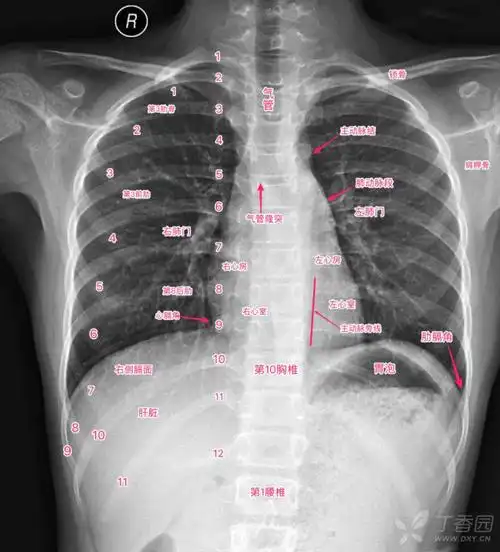

超详细胸片教学不信你还学不会